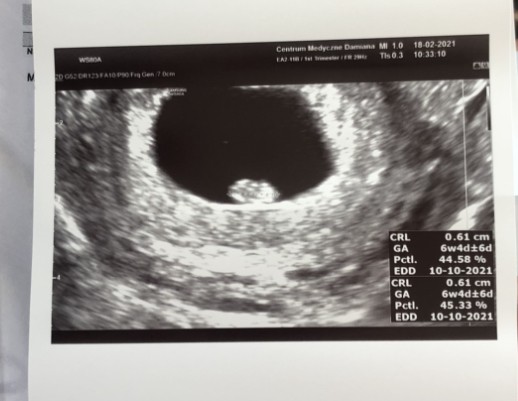

Gs to pecherzyk. On ma 0.9 cm na Twoim usg. Nie ma pomiaru zarodka (CRL). A na moje oko te dwie kropki to zarodek i pecherzyk żółtkowy.

Zobacz załącznik 1239734Ja już po wizycie, zarodek umiejscowiony w macicy, ma niecałe 1cm. Ale nie wiem czy widzicie różnice miedzy zdjęciami. Albo to poniżej to krwiaczek, albo drugi zarodek [emoji15] jestem przerażona! Dziś wyszło z usg 4+5 kolejna wizyta za 2 tyg no i dostałam Dupasthon 2x1

Tak jak wspomniałam u góry. Wymiar koleżanki dotyczy pęcherzyka a Twój zarodka [emoji854]

Wszystko jest w normie. Miałam tutaj właśnie na myśli porównanie do drugiej dziewczyny, bo to jednak spora różnica. A kwestia nazewnictwa. Pamiętam, że mi lekarz właśnie w pierwszej ciąży na początku mówił wielkość pęcherzyka, a dopiero później zarodka, gdy się pojawił. Z drugiej strony te wielkości są tak małe, że wystarczy, że lekarz przesunie delikatnie ręką i zaznaczy trochę bliżej lub dalej, a wielkości mogą się znacząco zmienić, więc trzeba to też mieć na uwadze, żeby się za bardzo nie stresować, bo może to być po prostu błąd w pomiarze 😉

Ja słyszałam, że dzieci ja początku rosną wszystkie tak samo. Dlatego łatwo jest określić tc na podstawie USG. Pytanie czy lekarz mówił, że pęcherzyk tyle ma, czy że zarodek tyle ma

Teraz to mnie zabiłaś pytaniem. Najpierw mnie na koźle zbadał później zrobił usg i mówił ze jest pęcherzyk w sumie który przekształca się w zarodek, ze komputer dopiero od 1cm chyba obliczy, ale udało mu się i było 4+5. Powiedział na początku ze to możliwe ze krwiak, nic o zarodku nie wspomniał dopiero później jak już usiedliśmy porozmawiać, ogólnie mówi żeby się nie przejmować i nie martwić gdyby pojawił się krew taka ciemna, tylko jak pojawiła by się jasna... przepraszam wszystko pokręciłam, ale dostałam szoku !